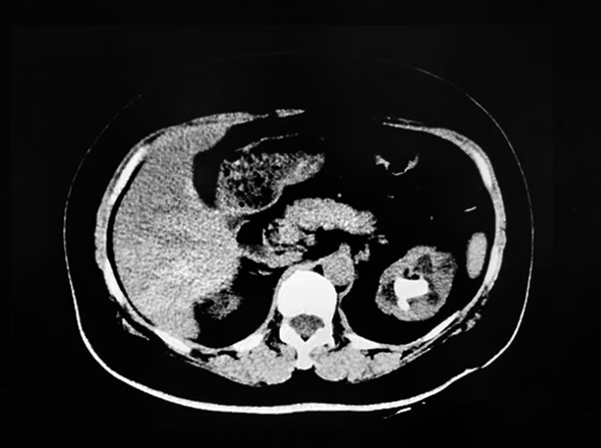

手术周期间,李虎林教授再次展示了他精湛熟练的临床技巧,连续为两名患者进行了PCNL。其中,一名45岁的患者左腰反复疼痛已有十余年,术前CT影像显示其左肾存在铸型结石。李虎林教授综合评估患者病情及身体情况后,制定了局麻下的免人工肾积水左侧PCNL,帮助患者规避全麻风险,助力患者快速康复。

李虎林教授将患者CT影像数据导入VENUS,VENUS高速融合影像并快速完成高精度AI自动化配准,快速、精确地“还原式”3D呈现人体解剖结构及肾脏、结石位置。李虎林教授精准定位患者结石区域,并在VENUS的可视化实时引导下快速建立穿刺的安全通道,高效地为患者进行“清石”。